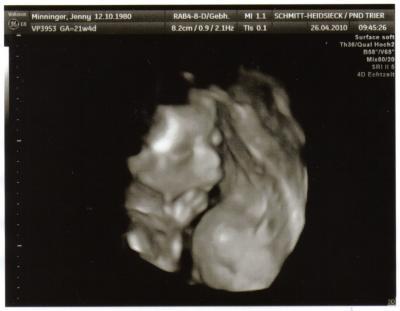

Hi Mädels, war heute dann auch noch zum Organ-Screening! Ist alles top, alles dran, alles super durchblutet. Krümel weiterhin sehr groß: jetzt etwas mehr als 26cm und ca. 465 gramm schwer. Und wir haben ein definitives Outing bekommen. Aus unserem Jungen wurde heute ein Mädchen! Bekomm seitdem das Grinsen nicht mehr ausm Gesicht. Mein Freund dagegen ist total neben der Spur...hihi... Das muss er erst mal verdauen! LG Jenny

Bild zu Heute Organscreening u. 3D Bild - Forum für September - Mamis

Hallo, also das hat ca. 20 Minuten gedauert. Und der 3D Anteil war nur gering. Im Prinzip nur kurz bis die Kleine endlich mal die Hände vorm Gesicht weggenommen hatte für das Bild. Hab ja auch kein 3D bezahlt. War also nur ein kleiner Bonus gewesen. Viel Spaß morgen LG Jenny

WOW, klasse Bild!!! *gg* Das grinsen konnte ich mir eben auch nicht verkneifen... Herzlichen Glückwunsch zum Mädchen!!!! Hach, was ´ne Überraschung!!! ;-)